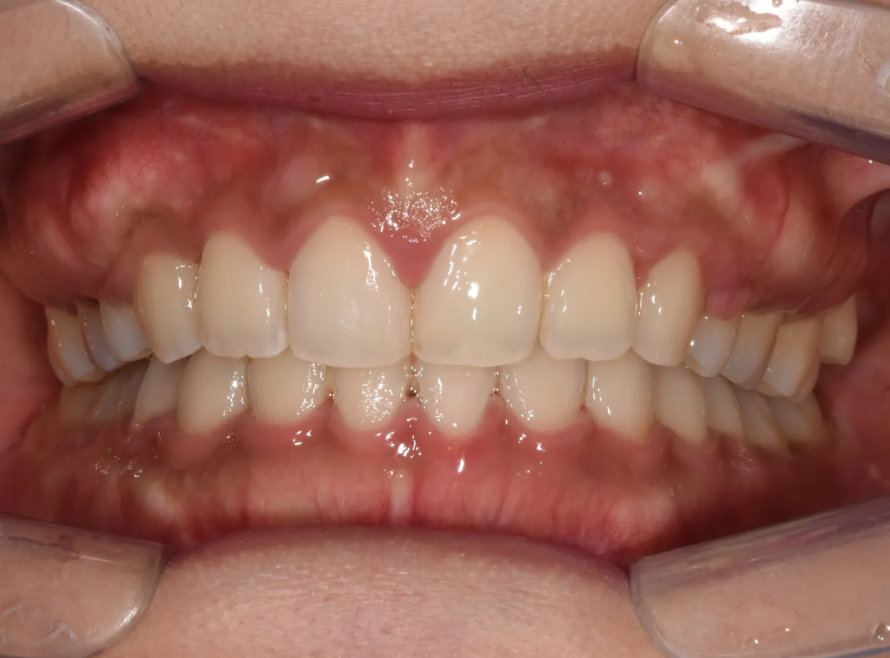

치료 완료: 과개교합 해소 및 후방이동 결과

2년에 걸친 치료가 드디어 완료되었습니다. 과개교합이 완전히 해소되어, 윗니가 아랫니를 덮는 양(수직피개)이 정상 범위로 돌아왔습니다. 처음 내원하셨을 때 윗니가 아랫니를 거의 완전히 덮고 있던 것과 비교하면 정말 큰 변화입니다.

윗니와 아랫니 각각 역시 매우 예쁘게 배열된 모습을 확인하실 수 있습니다.

위쪽 작은어금니 발치 공간을 이용한 후방이동으로 앞니 돌출감도 해소되었습니다. 환자분이 가장 고민하셨던 '토끼이빨' 인상이 사라지고, 입술 돌출감도 개선되어 자연스러운 스마일라인이 완성되었습니다.

이번 케이스는 비수술 교정만으로도 심한 과개교합을 충분히 해결할 수 있다는 것을 보여주는 대표적인 사례입니다. 전후 사진을 비교해 보시면 그 변화를 확실히 느끼실 수 있습니다. 우선 아랫니를 완전히 덮고 있던 윗니가 올라가면서 이를 다문 모습이 확연히 예뻐졌습니다. 당연히 토끼이빨 느낌도 완전히 사라졌습니다.